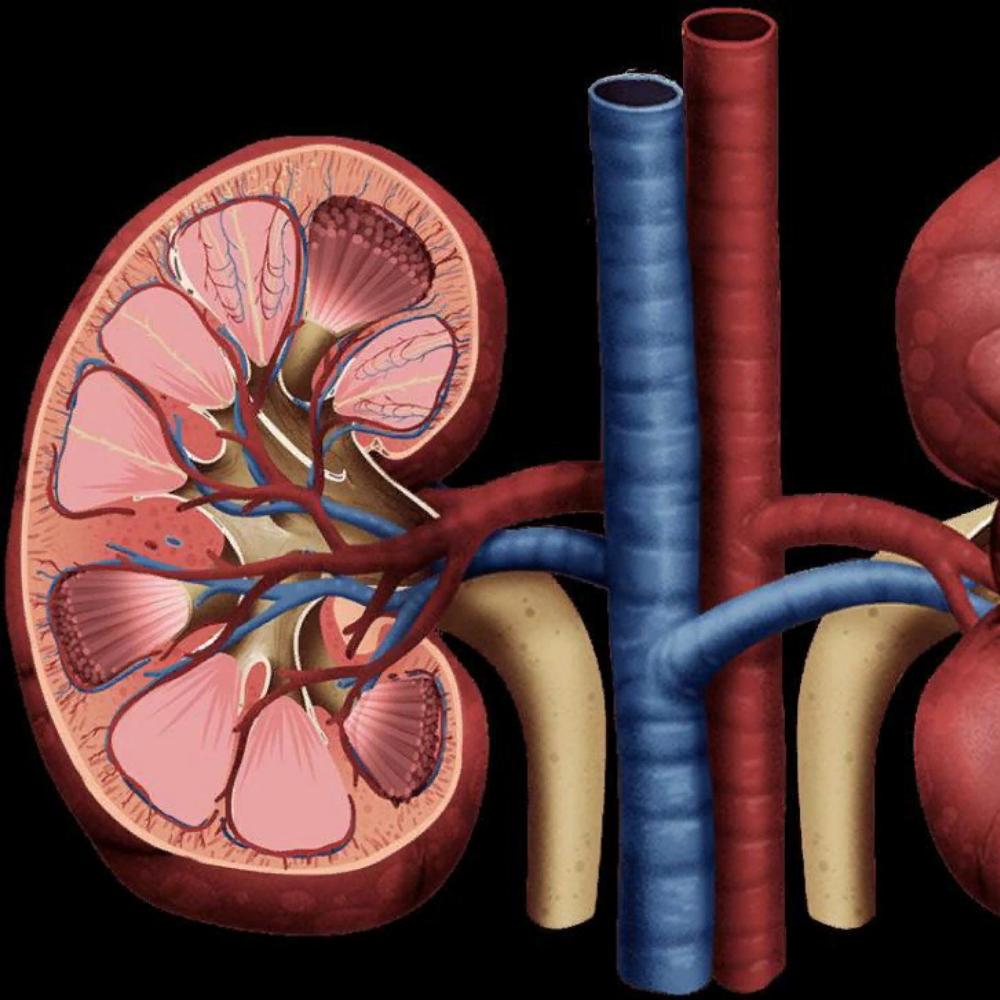

Строение почек человека: Фото и описание